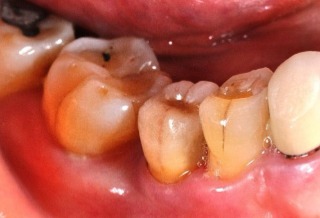

臨時假牙/牙齦塑形器

常常覺得植牙完後會卡食物嗎? 現在用牙齦塑形器就可以避免了。

在安裝正式植牙假牙前,會先按照電腦規劃的結果設計,製作臨時假牙/牙齦塑形器,用來塑形牙肉使其恢復至正常的牙縫型態,避免日後發生卡牙縫的問題。